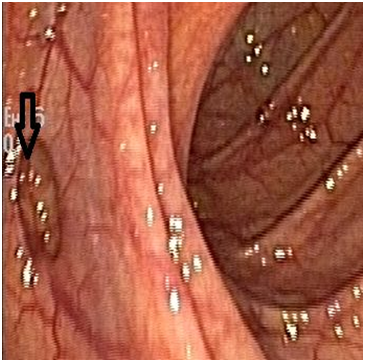

A 53 year old male vegetarian, not diabetic or hypertensive and did not have a history of cardiovascular, hepatic or kidney disease, presented to us with vague pain and worsening swelling of both lower limbs since 1 week. Physical examination was unremarkable except for bilateral tender pitting edema of feet, legs and thigh. Investigations showed Hb 116g/L,WBC count 8.9 X 109/L, platelet 301 X 109/L, ESR 72mm/hr, blood urea nitrogen 21mmol/L, serum creatinine 132 micromol/L, Urine albumin nil. Saturation was 98% in room air. Chest X ray was unremarkable. Venous doppler study of lower limbs unmasked DVT involving bilateral saphenofemoral, superficial popliteal and popliteal veins with normal arterial doppler. Tc-99m lung perfusion was normal. LFT, fasting lipid profile, electrolytes and thyroid function were normal. HIV, HBsAg and anti HCV were negative. Protein C, protein S activity, antithrombin III, factor V leiden mutation, APLA were unremarkable but a high total plasma homocysteine of 29.76umol/L(5.46-16.20umol/L). B12 level was low (188pg/ml) and he was given IM. methylcobalamin 1000mcg for 7 days. CT Venogram showed chronic thrombosis of the IVC and bilateral renal veins with acute thrombosis in bilateral common iliac, external/internal iliac, bilateral common femoral and superficial femoral veins (Figure 1).

Figure 1 CT Venogram showed hypoplastic IVC as depicted by thinned out IVC with chronic thrombosis(white arrows) with acute thrombosis in bilateral common femoral/superficial femoral veins depicted by distended veins when compared to the arteries(black arrows).